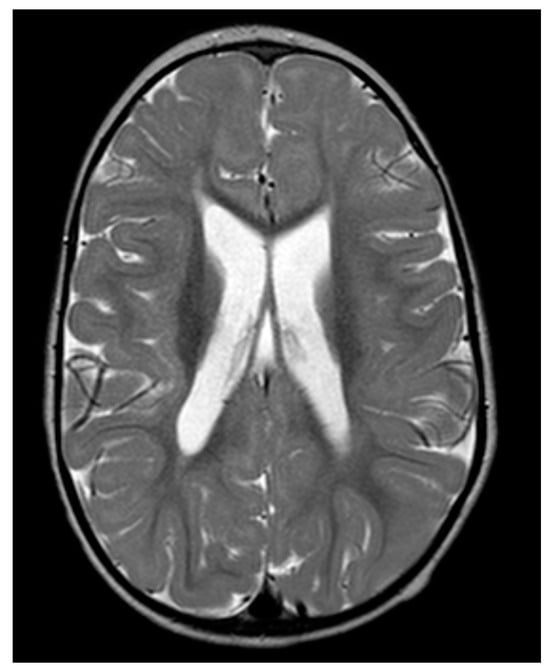

2.1. Case Description